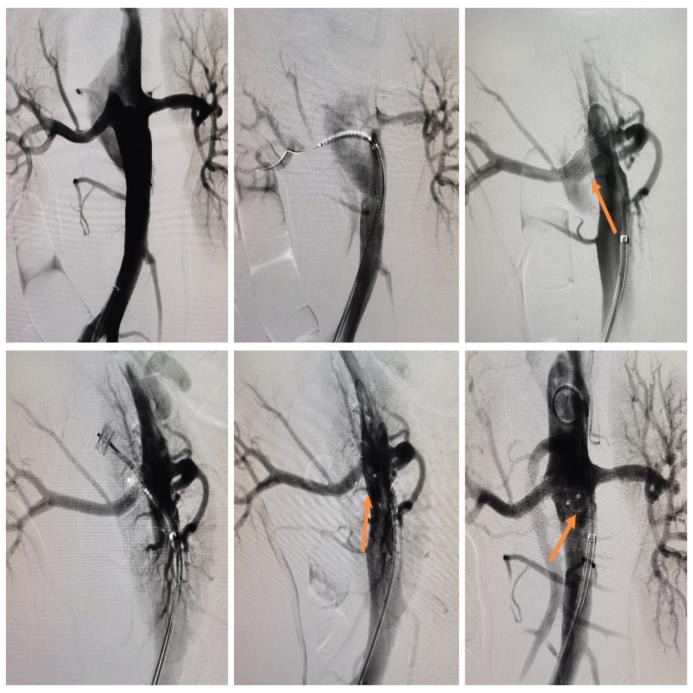

经过对病变特点分析和数据测量,血管外科团队制定了创新性的技术方案,决定使用血管塞封堵升主动脉及腹主动脉夹层破口。另有一破口位于肾动脉内,决定使用一枚肾动脉支架封堵肾动脉破口。术中穿刺一侧股动脉,用合适规格的2枚血管塞分别成功封堵了升主动脉及腹主动脉破口,并使用1枚覆膜支架重建右肾动脉并封堵其破口,术中造影显示夹层隔绝良好。

图2.术中DSA(数字减影血管造影)影像

(箭头所指为升主动脉破口及血管塞)

图3.术中DSA影像(箭头所指为腹主动脉破口及血管塞)